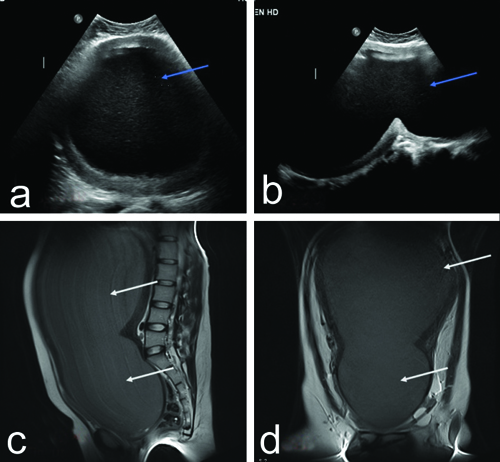

Clinically, a diagnosis of haematometrocolpos was made and the patient underwent ultrasound of the abdomen followed by Magnetic Resonance Imaging (MRI). The ultrasonography revealed a large abdominopelvic cystic mass representing a grossly distended uterine cavity and vagina, which showed echogenic contents [Table/Fig-1a,b]. There was narrowing at the level of the vagina, which was confirmed on MRI, with the endometrial and vaginal cavities showing T2 iso to mildly hyperintense contents suggestive of blood products/proteinaceous contents. The size of the distended uterus and vagina measured approximately 35×18 cm [Table/Fig-1c,d]. Postoperative changes were noted in the vagina with the loss of normal vaginal contour. There was associated mild left hydroureteronephrosis due to obstruction of the left ureter by haematometrocolpos. The patient underwent ultrasound-guided haematometrocolpos drainage with cystoscopy. The patient was placed in a lithotomy position and the surgical site was painted and draped. Under general anaesthesia and aseptic conditions, an incision was made below the urethra and the plane was dissected with ultrasound guidance, following which 4.5 litres of altered tarry chocolate-coloured blood was drained. Postsurgery, a per rectal examination was done to ensure the patency of the rectal mucosa. Foley’s catheter (22G) was inserted through the septum for continuous drainage. The patient received packed red blood cell transfusion preoperatively and postoperatively to improve the haemoglobin level. The abdominal distension and pain significantly reduced after drainage [Table/Fig-2a,b]. Post-drainage ultrasound images showed an empty endometrial cavity and a bulky uterus with heterogeneous echotexture [Table/Fig-2c,d]. Furthermore, the patient was referred to the plastic surgery department for vaginal reconstruction.

a,b) Ultrasound pelvis images showing grossly distended uterus and vagina with echogenic contents suggestive of blood products (blue arrows). c,d) T2 weighted sagittal and coronal MRI images showing grossly distended uterus and vagina extending upto epigastrium showing mildly T2 hyperintense contents (white arrows) suggestive of haematometrocolpos.